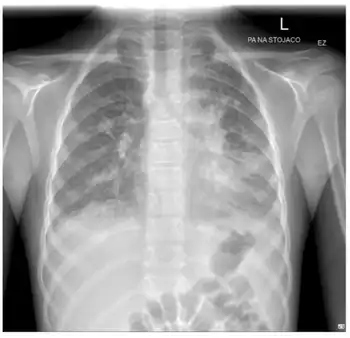

Doxycycline can be used for treating Mycoplasma pneumonia, which usually presents with persistent, incessant cough that lasts for several weeks and shows interstitial pulmonary infiltrates on a chest x-ray.[42]